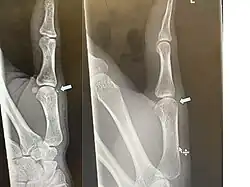

Avulsion fracture of the proximal middle phalanx on the palm side

Avulsion fracture of a fingertip bone